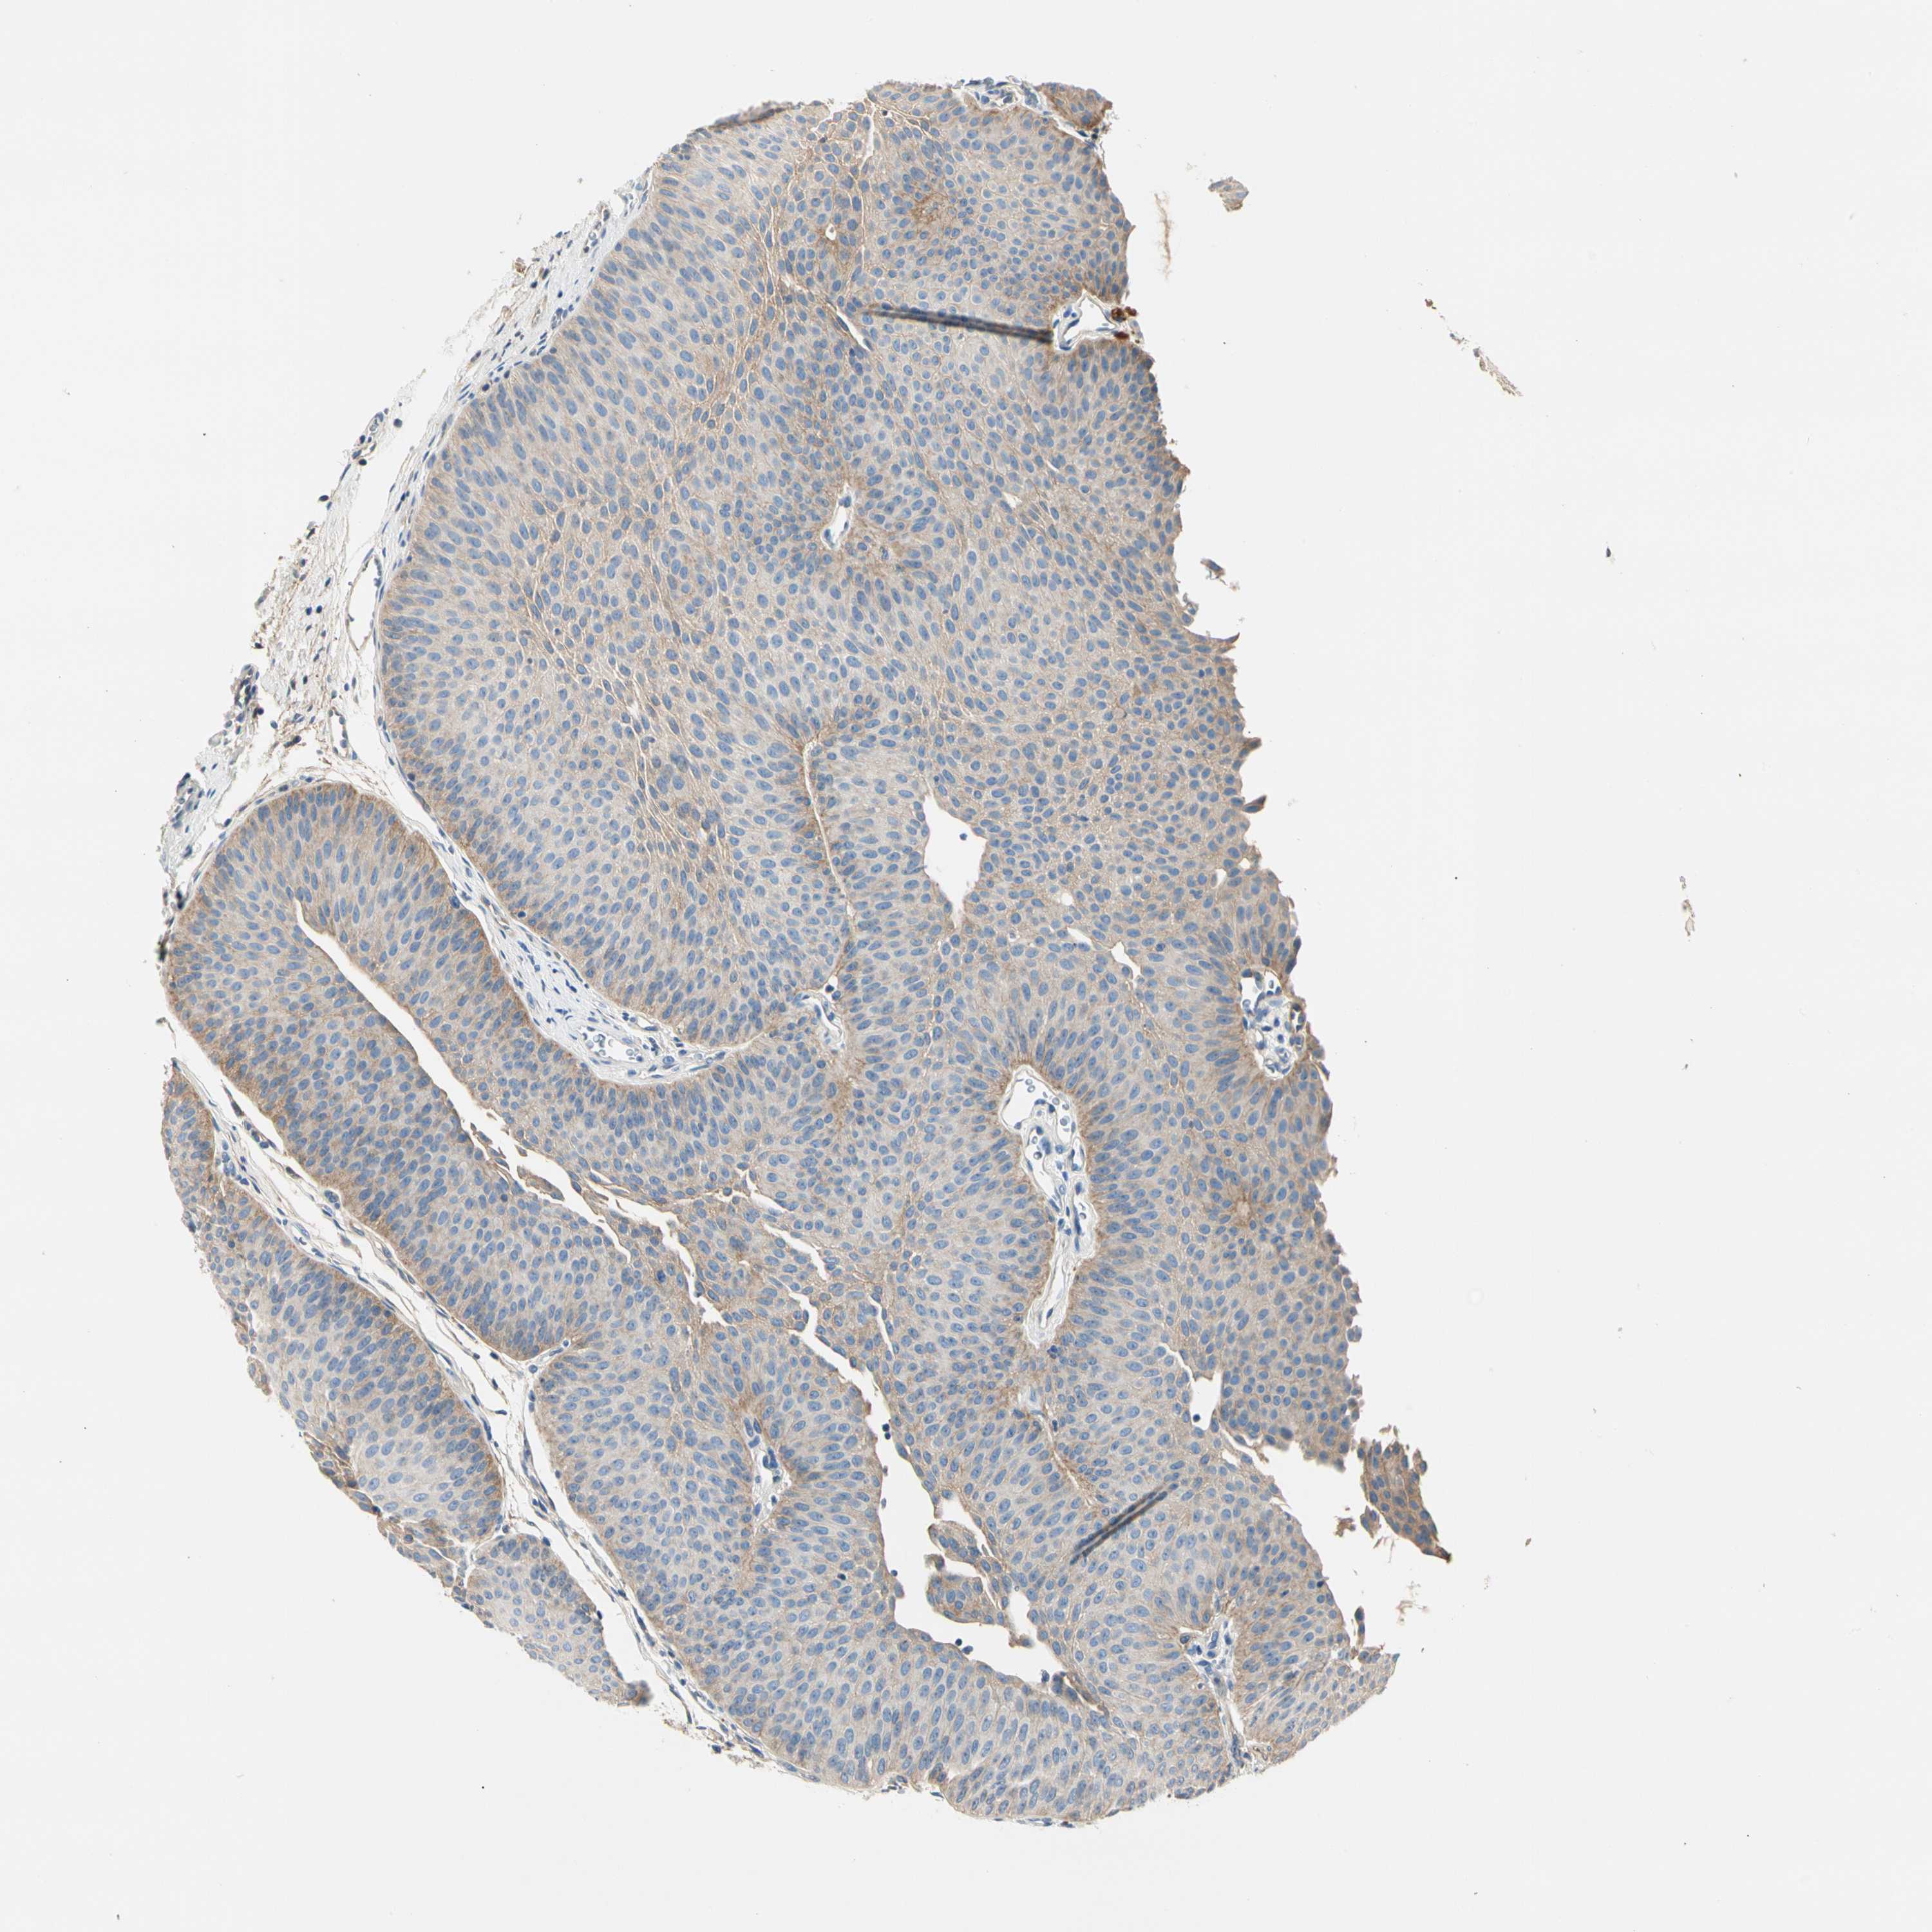

UROTHELIAL CANCER - Protein expressioni

A mouse-over function shows sample information and annotation data. Click on an image to view it in a full screen mode. Samples can be filtered based on level of antibody staining by selecting one or several of the following categories: high, medium, low and not detected. The assay and annotation is described here.

Antibody stainingi

Antibody staining in the annotated cell types in the current human tissue is reported as not detected, low, medium, or high, based on conventional immunohistochemistry profiling in selected tissues. This score is based on the combination of the staining intensity and fraction of stained cells.

Each image is clickable and will lead to virtual microscopy that enables deeper exploration of all samples and also displays staining intensity scores, fraction scores and subcellular localization as well as patient and tissue information for each sample.

Antibody HPA008257

Antibody CAB018971

Staining

High

Medium

Low

Not detected

Intensity

Strong

Moderate

Weak

Negative

Quantity

>75%

75%-25%

<25%

None

Location

Nuclear

Cytoplasmic/membranous

Cytoplasmic/membranous,nuclear

Urothelial carcinoma, Low grade

Urothelial carcinoma, High grade